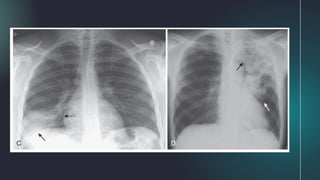

Patient positioning: Lateral decubitus

Effect of Patientpositioning